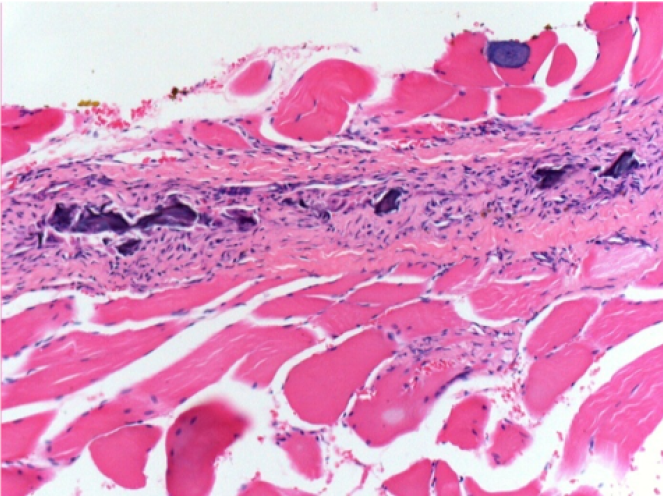

10 días después de la inyección de Endopeel

10 días después de la inyección de Endopeel 0,1 ml en el músculo pretibial derecho.

Aquí puede ver la formación de las vacuolas que están rodeadas de linfocitos. Las vacuolas son diferentes a la necrosis tisular. La presencia de linfocitos está relacionada con la permeabilidad de las membranas celulares.

L : Control-100xD10

R:100xD10

R :200xD10

R :400xD10